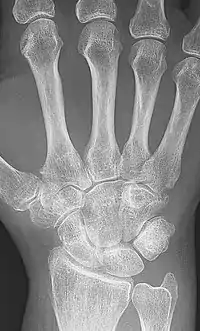

X-rays of the hands and feet are generally performed when many joints affected. In RA, there may be no changes in the early stages of the disease or the x-ray may show osteopenia near the joint, soft tissue swelling, and a smaller than normal joint space. As the disease advances, there may be bony erosions and subluxation. Other medical imaging techniques such as magnetic resonance imaging (MRI) and ultrasound are also used in RA.[20][63]